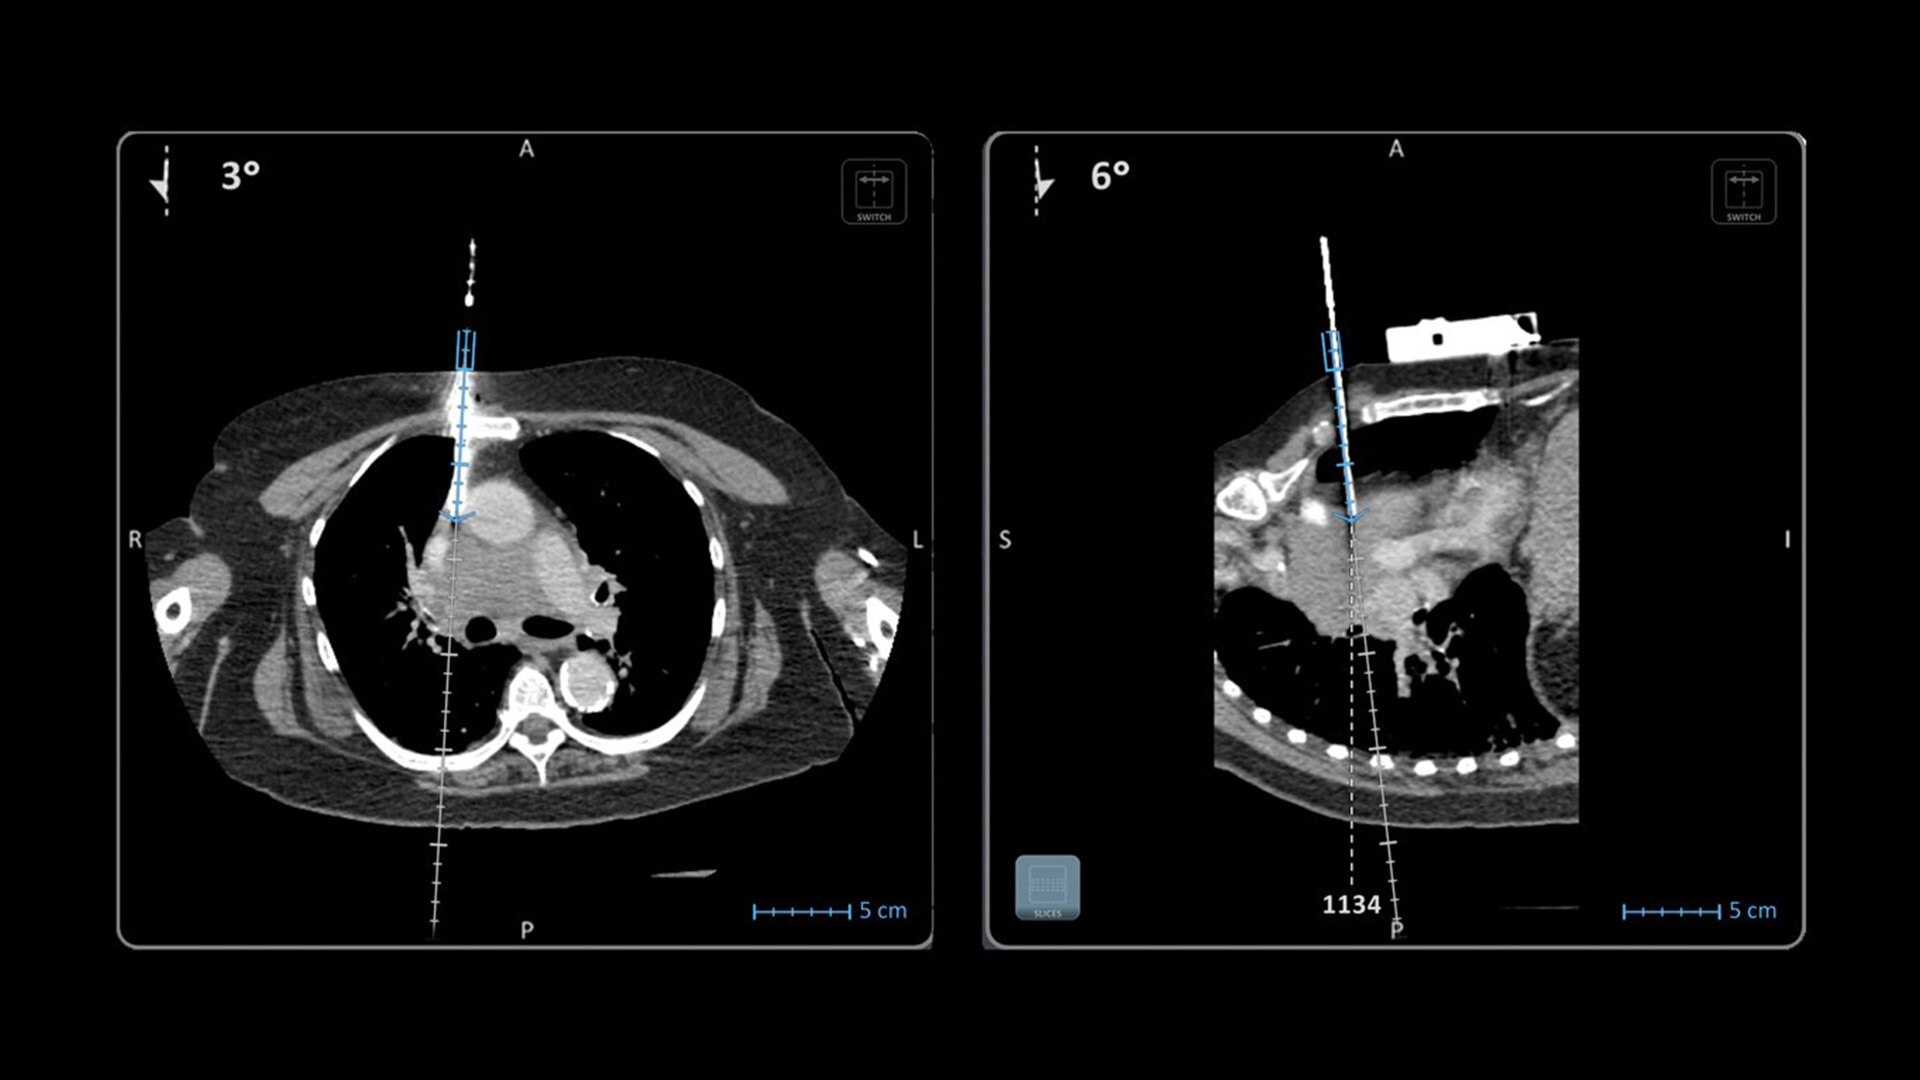

Imactis® CT-Navigation™

Planning and navigation solution for interventional percutaneous radiology that can increase procedure accuracy, reduce time, simplify workflow and reduce dose.¹

In interventional radiology, the success of the percutaneous procedure depends on correct needle positioning. The Imactis system helps the radiologist place one or more needles with great accuracy, in less time and with fewer control scans.

Imactis enables you to find the ideal path to the target.

With real-time image reconstruction, live interactive navigation and no limit in angulation, the optimal clinical choices are clear.

Live 3D needle tracking, precise reproduction of your planned trajectory and continuous needle depth measurement help ensure optimal needle placement.